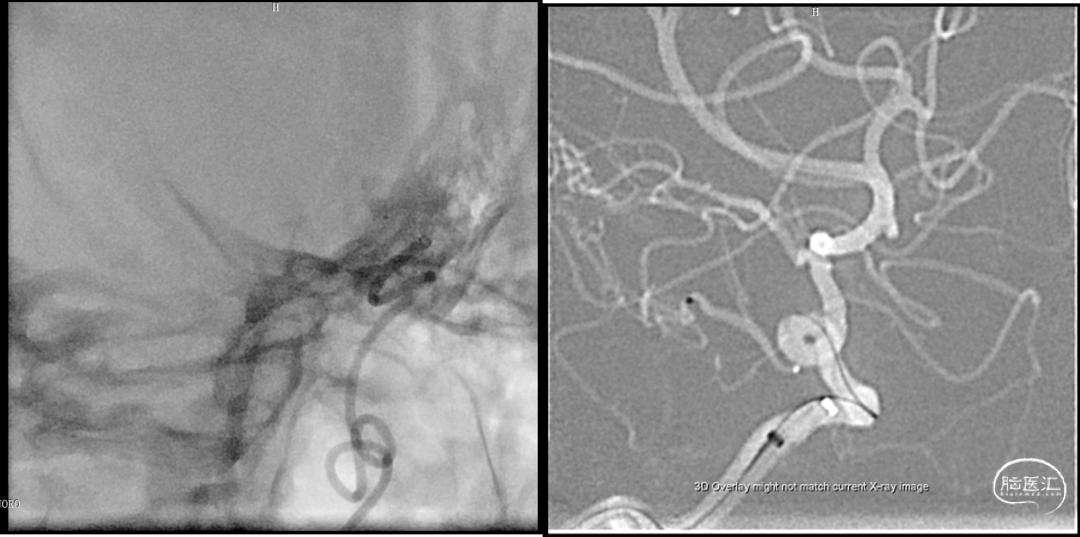

2023-08-30

术后造影:假性动脉瘤消失

2023-08-31

术后CT

2023-09-01

术后MR未见该中央新发支梗塞

后交通动脉在向后稍内行走的过程中发出两组约2 -8条(以4条为多见)细小的中央支(图1)。前组供应丘脑下部、丘脑腹侧部;视束前部和内囊后肢。后组主要供应丘脑底核。这些中央支之间虽然存在吻合,但其中一支阻塞后,因有效的侧支循环难以建立,故多产生相应供应区的梗死。该病例栓塞假性动脉瘤所在中央支没有症状,考虑为假性动脉瘤导致该中央支缺血耐受和血管代偿。